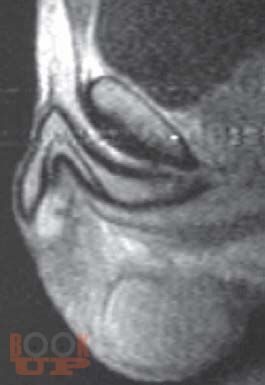

Монография посвящена проблеме повышения эффективности диагностики и хирургического лечения различных заболеваний мужских половых органов. Авторы приводят новые возможности методов лучевой диагностики и оригинальные методики малоинвазивного хирургического лечения заболеваний полового члена, органов мошонки, предстательной железы. Книга рассчитана на урологов, андрологов, хирургов, лучевых диагностов, а также будет полезна широкому кругу читателей.